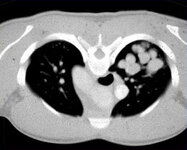

Aspergilose broncopulmonar alérgica

Tomografia computadorizada (TC) do tórax em um paciente com aspergilose broncopulmonar alérgica (ABPA): sombra em "dedo de luva" devida à impactação mucoide na bronquiectasia central em um paciente com asma

Do The Radiology Assistant: Chest - HRCT Part 1; usado com permissão